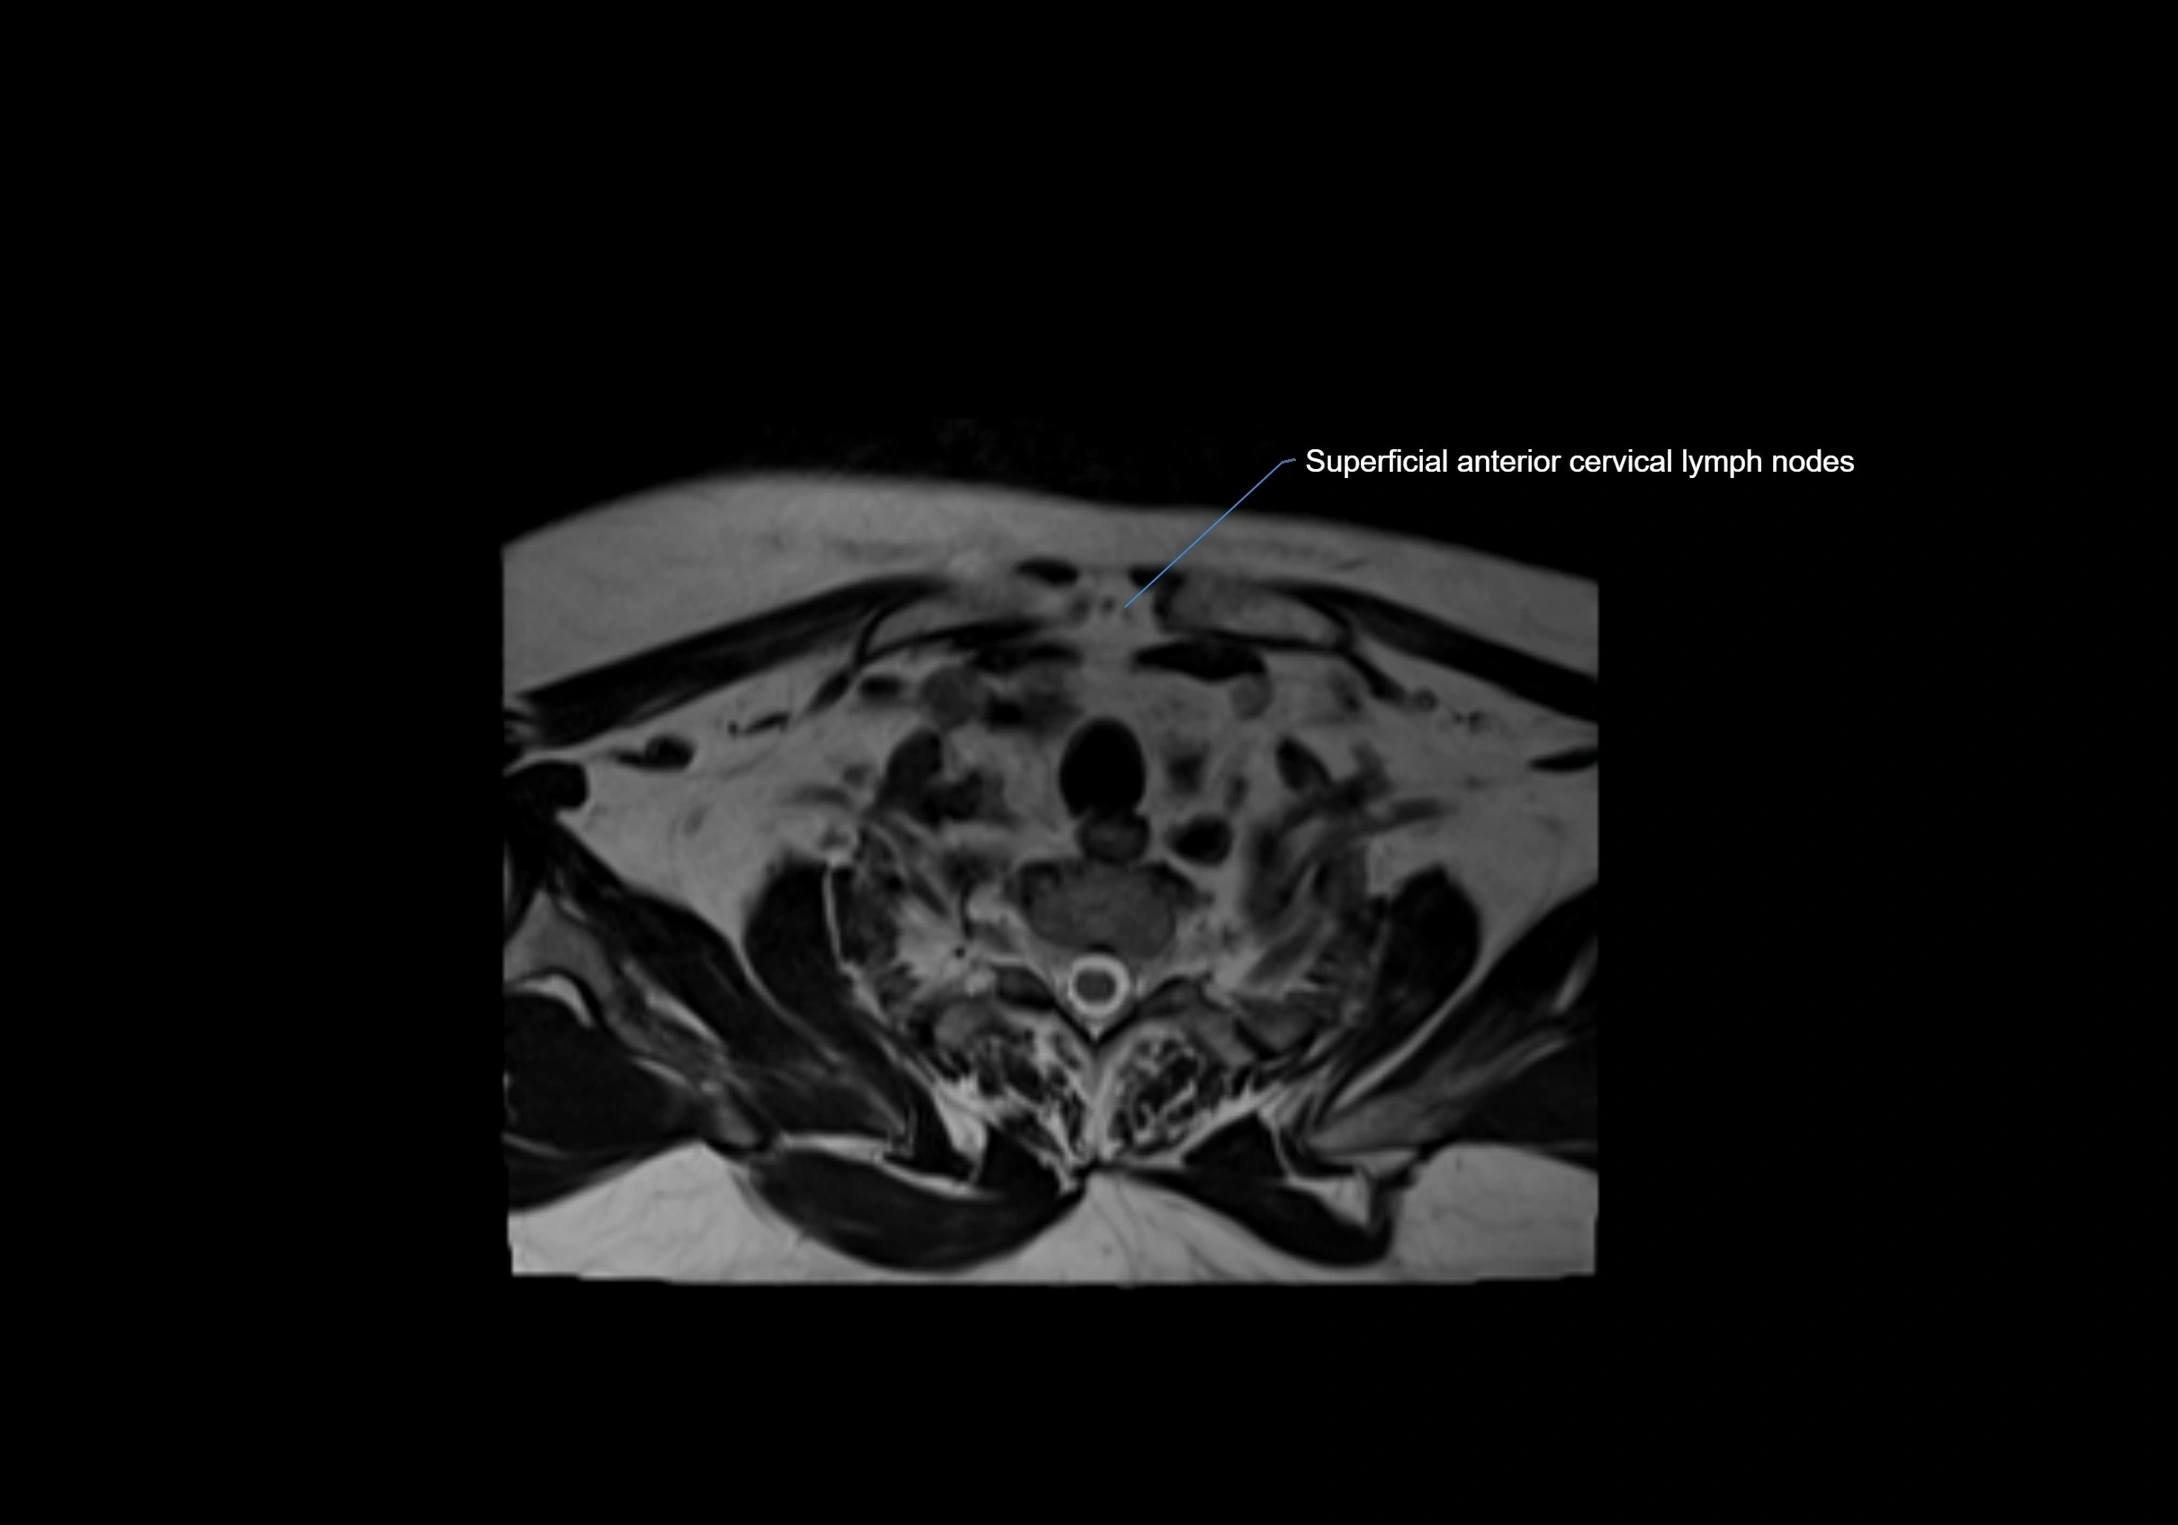

Location

• Found along primary lymph node chains, including preauricular, submandibular, parotid, and occipital regions

• Embedded in subcutaneous fat or superficial fascia, often lateral or posterior to primary nodes

• Variable in number; may occur unilaterally or bilaterally, depending on individual anatomy

MRI Appearance

CT Appearance:

• Nodes appear as small, soft tissue density structures embedded in subcutaneous fat near primary lymph nodes

• Surrounded by air in adjacent facial cavities or normal soft tissue, providing natural contrast

• Enlarged or pathological nodes appear as well-defined or irregular soft tissue masses

• CT is particularly useful for preoperative assessment, infection evaluation, or detection of metastatic spread

MRI images